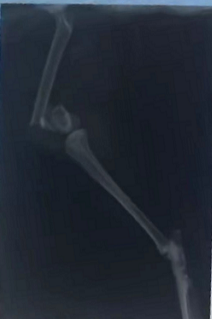

犬骨折,如图(56-58题共用题干)(2021B卷临床41-43)手术治疗时其手术通路的皮肤切口位于

2022xsGeycgBxi1660809559.png

• A. 股骨外侧切口

• B. 股骨内侧切口

• C. 膝关节外侧切口

• D. 肱骨外侧切口

• E. 肱骨内侧切口

标记 纠错